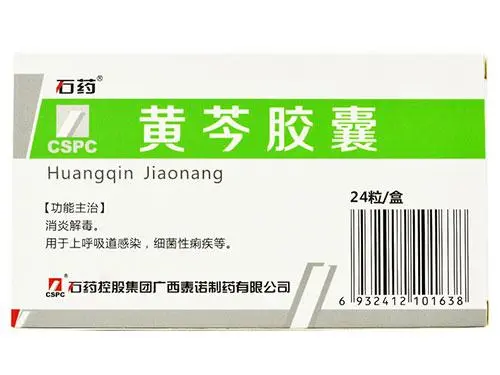

药物和治疗:一些药物和治疗也可能会影响夫妻的夫妻生活频率和质量。例如,抗抑郁药物、避孕药等可能会影响欲望和性能力,从而影响夫妻生活的频率和质量。

1、抗抑郁药物:用于治疗抑郁症和其他精神疾病。一些抗抑郁药物可能会降低欲望和性能力,从而影响夫妻的夫妻生活频率和质量。这是因为抗抑郁药物可能会影响大脑中的神经递质,从而降低欲望和性能力。

2、避孕药:用于避孕。一些避孕药可能会影响雌激素和孕激素水平,从而降低欲望和性能力。一些避孕药可能会导致私处干燥和不适,从而影响夫妻的夫妻生活频率和质量。

其他一些药物和治疗也可能会影响夫妻的夫妻生活频率和质量。例如,一些降压药、利尿剂、抗过敏药、抗癌药等可能会影响欲望和性能力。一些治疗方法,例如放疗、化疗等,也可能会导致欲望和性能力下降。

如果夫妻们正在服用药物或接受治疗,他们应该咨询医生或药剂师,了解药物或治疗可能产生的副作用,包括对夫妻生活的影响。如果药物或治疗导致夫妻生活频率和质量下降,夫妻们可以与医生协商,寻求替代治疗方法或调整药物剂量。